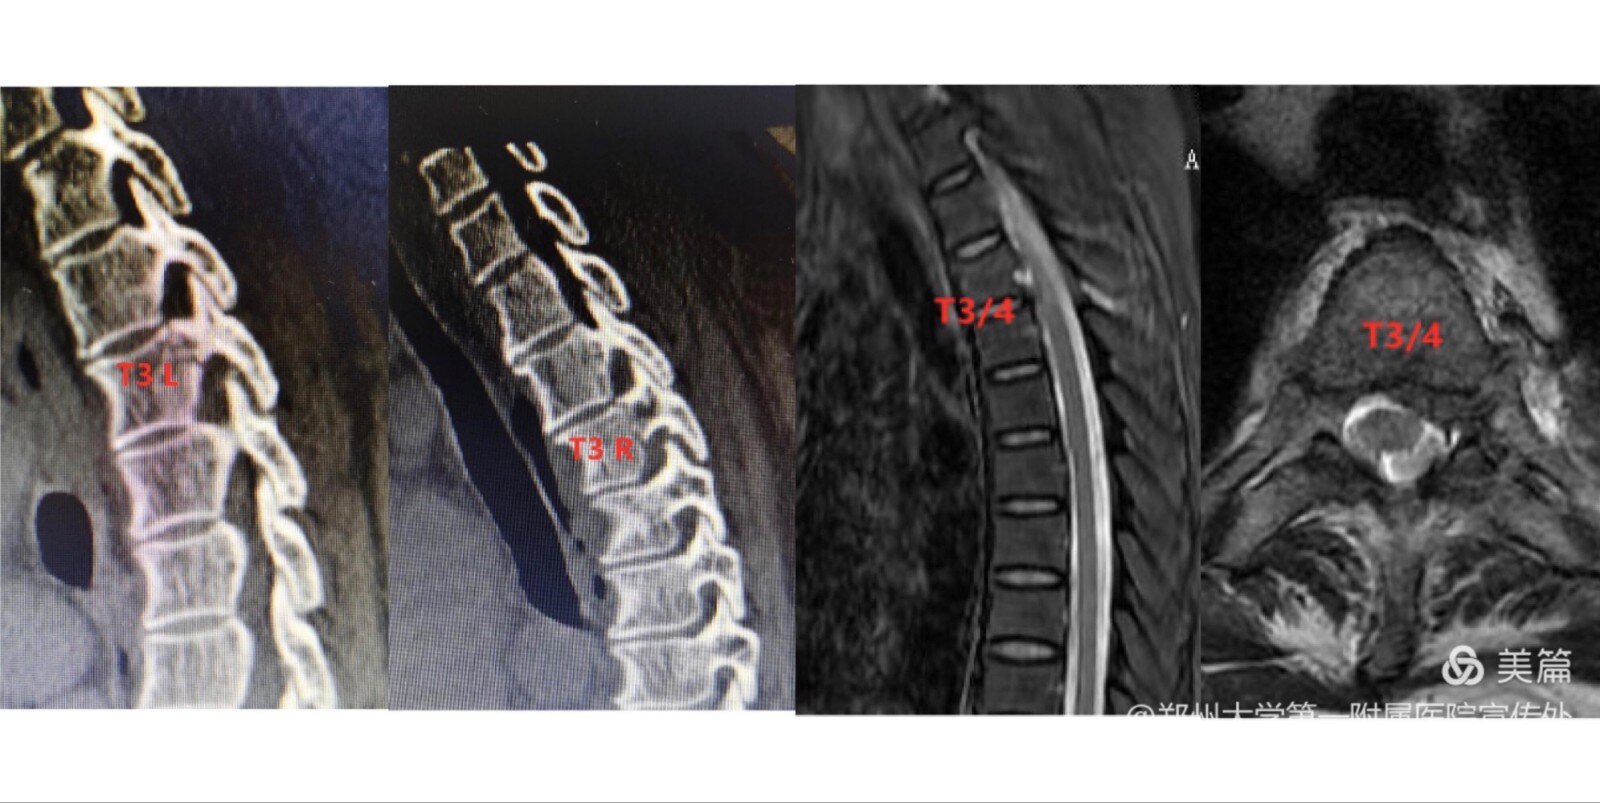

赵女士,54岁,因外伤致胸背部疼痛伴左侧肢体麻木,保守治疗后病情不断加重,到惠济院区骨科住院治疗。入院检查后确诊:1.胸3-4椎间盘突出症;2.胸3双侧椎弓根不全骨折。根据患者病情,经过术前充分讨论,黄宗强教授团队为患者量身定制了个性化手术方案。手术采用一种全新的脊柱微创新技术单侧双通道内镜技术,术中在患者手术部位做2个7mm左右的小切口,出血仅几十毫升,术后患者左侧肢体麻木感较前明显好转,目前正在顺利康复中。

据黄宗强教授介绍,有临床症状的胸椎间盘突出症发生概率较低,仅占所有椎间盘突出症的0.25%~0.75%,且发生于T3/4椎间盘之上的更少见;由于胸椎管的容积较小,可操作空间有限,胸部脊髓的耐受性也相对较差;因此将UBE技术应用于胸椎间盘突出症的治疗存在较大的挑战。但本例手术的成功实施表明UBE技术治疗胸椎间盘突出症在操作上具有可行性,且效果满意。UBE技术不同于显微镜技术或椎间孔镜技术,不仅具有微创的效果,还能达到传统开放手术的操作范围及视野,其特有的优势和价值使其在微创治疗胸椎间盘突出等胸椎疾病方面具有较为广阔的应用发展前景。